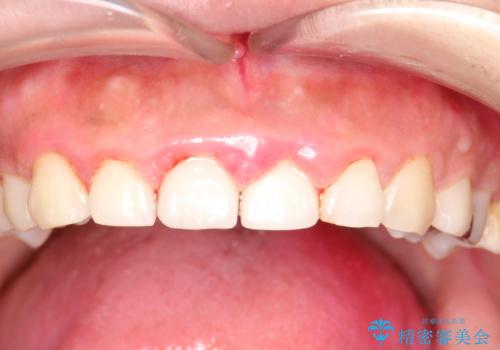

終了時

かなり久しぶりの歯科医院との事で、全体的に古くからの歯垢・歯石が多く付着していたため、自費クリーニング(PMTC)60分コース・歯周ポケット検査(保険適応)を行いました。

磨き残しが放置されると、そこで病原菌が繁殖し始めます。よって歯肉に炎症が生じ、歯周病の原因になることがあります。

定期的に、歯周病検査や専門的なクリーニングをすることで、早期発見につながります。